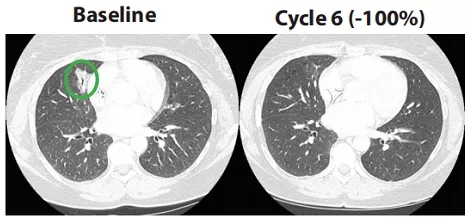

49岁的W女士在2012年确诊为ROS1融合IV期NSCLC,接受克唑替尼治疗5年出现耐药,2016年检测发现一种新的突变,ROS1G2032R,于是开始接受保底药物劳拉替尼的治疗,仅4个月就出现耐药,临床上没有适合的治疗方案,W女士参加了repotrectinib的临床试验,在用药第二周出现部分缓解,第六周100%的肿瘤全部消退,截至文献发表时仍在接受治疗。